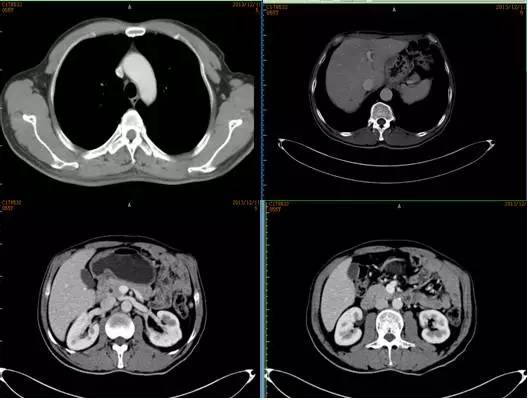

影像学检查

腹部CT平扫+增强(2009-12-22我院)示:肝脏多发转移瘤,腹膜后淋巴结转移。胸部CT(2009-12-21我院)示左腋窝淋巴结肿大,转移可能性大。

2周期后复查CT

2013年12月复查